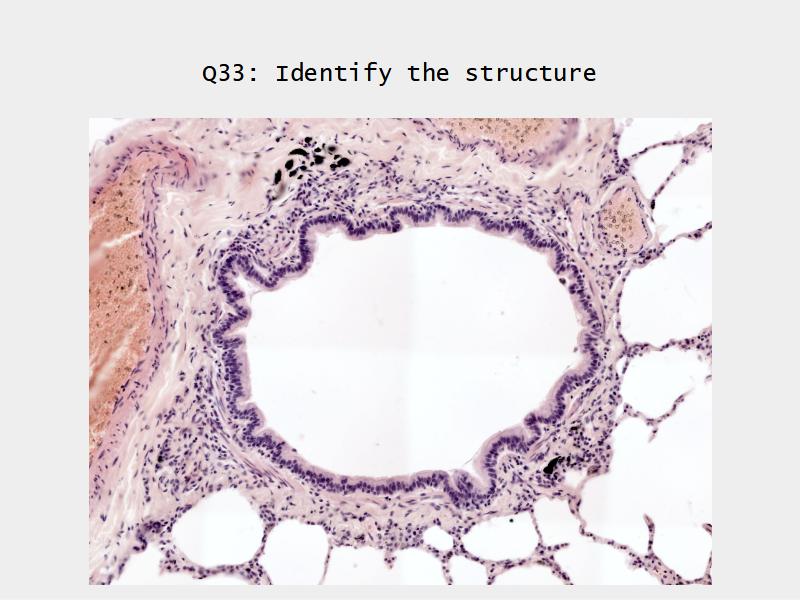

Bronchi - Transitions

- Intrapulmonary bronchi

- Irregular cartilage

- Respiratory epithelium

- Glands

- Bronchioles

- Smooth muscle REPLACE cartilage

- Ciliated columnar > Ciliated cuboidal

- NO glands - goblet cells -> secretory cells